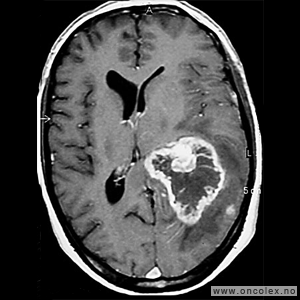

Glioblastomer

Glioblastom er den vanligste hjernesvulsten hos voksne, og cirka 220 norske personer får denne diagnosen hvert år. Samtidig er det en av de mest aggressive svulsttypene hvor i praksis alle pasienter på ett eller annet tidspunkt vil oppleve tilbakefall. Cirka 60 % av pasientene er menn og halvparten av pasientene er over 60 år. Behandling vil oftest være en kombinasjon av operasjon, strålebehandling og cellegift. For en del pasienter kan det være aktuelt å delta i studier med utprøving av ny behandling.

Spredningssvulster fra andre organer

Spredningssvulster (metastaser) til hjernen fra kreftsykdom andre steder i kroppen er mye hyppigere forekommende enn primære hjernesvulster (svulster som oppstår i hjernen). Med økende utbredelse av avansert bildediagnostikk, i første rekke MR, samt mer effektiv behandling av kreftsykdom ellers i kroppen, må man regne med at stadig flere spredningssvulster blir oppdaget og behandlet. Vanligst er spredning fra lungekreft, brystkreft og føflekkreft.